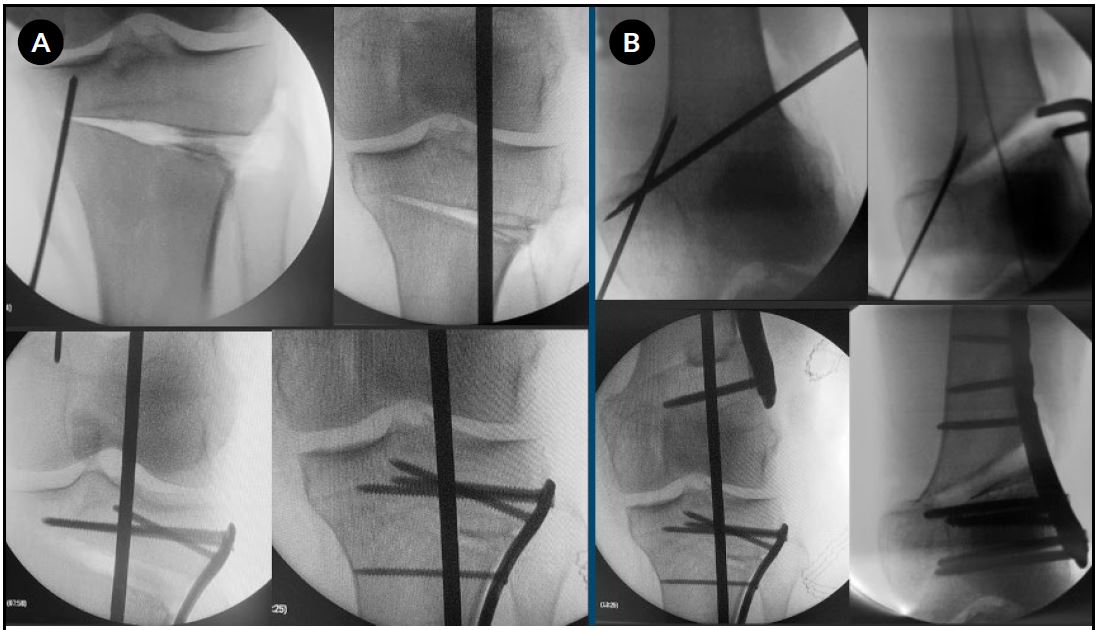

1. Osteotomía femoral distal lateral sustractiva (L-DFO)

Se efectúa un abordaje lateral por debajo del vasto lateral. Bajo control radioscópico, se colocan dos clavijas orientadas hacia el epicóndilo medial, definiendo un triángulo isósceles cuya base corresponde a la cuña planificada. Una clavija paralela a la cortical medial protege la bisagra ósea. El corte se efectúa con sierra oscilante. La cuña ósea extraída se conserva como injerto autólogo. La osteotomía se cierra progresivamente en valgo. La fijación se realiza con una placa bloqueada condílea, asegurando compresión en el foco (Fig. 2).

2. Osteotomía tibial proximal medial de apertura (M-HTO)

Se efectúa mediante un abordaje medial de la tibia proximal, entre la tuberosidad tibial anterior y el borde medial. Se protege el tendón patelar y el ligamento colateral medial superficial. Bajo radioscopia, se introduce una clavija guía desde la metáfisis medial hacia la cortical lateral, a nivel de la cabeza del peroné. Otra clavija protege la bisagra. El corte se efectúa con sierra oscilante y se completa con escoplos, con la rodilla en flexión para proteger las estructuras vasculonerviosas. La apertura se realiza de acuerdo con la corrección planificada. Se intercalan injertos óseos (autólogo y aloinjerto) y se fija con una placa bloqueada de tibia proximal, cuidando de no aumentar el slope tibial (ver Fig. 2).

Figura 2. A) Radiografías intraoperatorias de la osteotomía femoral distal lateral sustractiva (L-DFO): posicionamiento de las clavijas de Kirschner, extracción de la cuña ósea, posición de la placa y control final. B) Radiografías intraoperatorias de la osteotomía tibial proximal medial de apertura (M-HTO): posicionamiento de las clavijas de Kirschner, osteotomía con sierra oscilante y escoplos, colocación de injertos óseos, posición y fijación con placa.